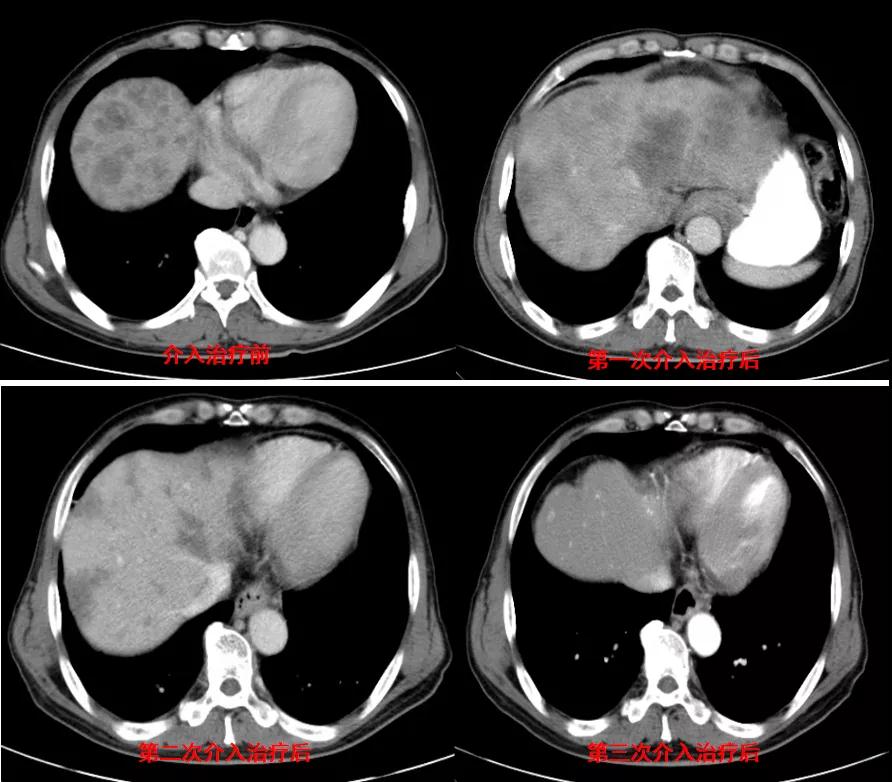

诊治经过:2020年12月16日患者行第二次经皮动脉化疗灌注栓塞术(铂类+氟尿嘧啶)治疗,并继续联合吡咯替尼治疗。结果见图3。

图3

诊治经过:2021年5月16日患者行第三次经皮动脉化疗灌注栓塞术(铂类+氟尿嘧啶)治疗,并继续联合吡咯替尼治疗。结果见图4。

图4

总结:本例患者为胃癌IV期,伴肝转移及淋巴结转移,经介入联合吡咯替尼治疗后,肝转移灶显著缩小。治疗前肿瘤标志为:癌胚抗原3574.3ng/ml、CA12-5 650U/ml、CA19-9 1212U/ml、CA15-3 333U/ml;治疗后肿瘤标志为:癌胚抗原7.6ng/ml、CA12-5 12.8U/ml、CA19-9 17.4U/ml、CA15-3 6.7U/ml。治疗后,肿瘤标志物显著降低,且腹部CT结果显示该患者肝转移病灶较治疗前明显减少。患者目前带瘤总生存达10个月,病情稳定。